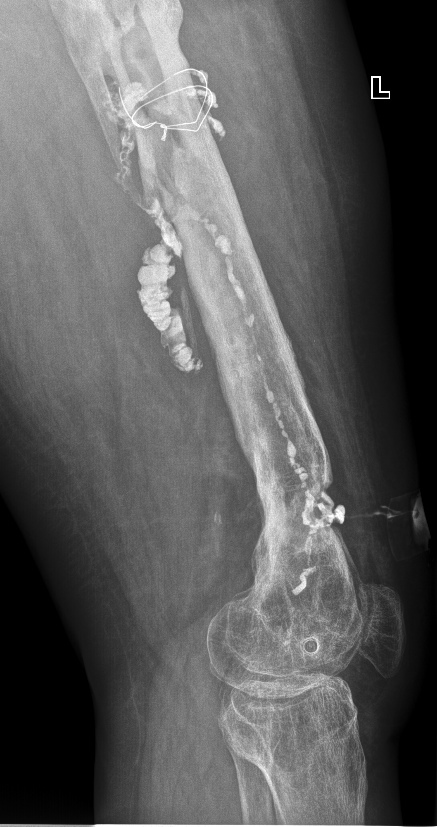

Женщина, 42 года, состояние после перелома левой бедренной кости в верхней и нижней трети, выраженный хронический остеомиелит. В верхней трети диафиза бедренной кости визуализируются остатки проволоки и булавовидной формы инородное тело.

Подозрение на свищ (свищевым ходом (свищем) называется канал, который соединяет место воспаления с какой-либо полостью и создает отток воспалительной жидкости (экссудата) или гноя. Это защитная реакция организма: выведение токсических (отравляющих) продуктов, вырабатываемых микробами).

Выполнена фистулография (методика рентгенологического исследования свищевых ходов с введением контраста) через свищевой ход на передней поверхности нижней трети бедра. Визуализируется свищевой ход, извитой формы. Контрастное вещество распространяется по костно-мозговому каналу бедренной кости от дистального метадиафиза до верхней трети кости (до места установки проволоки) с затеканием в мягкие ткани.

Снимки в прямой и боковой проекциях. Белые штуки вокруг костей - это контраст.